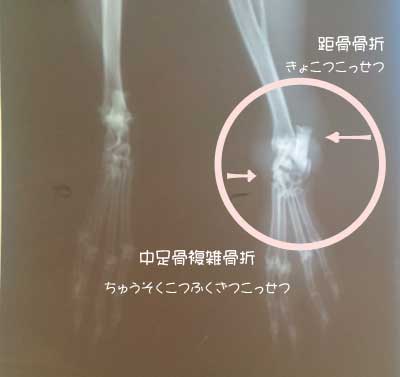

ミルの診断名

足根骨の短骨(小さな骨が規則正しく並んでいる)ところから、4本に別れていく中足骨

そこがぐしゃぐしゃになってしまいました。

そしてそのため、足指が開いてしまっています。

距骨とは、足根骨と字の如く足の一番下にある骨の一部ですが、人間だったら、踵の上に乗ってます。

うさぎは、絵を見る限りなんだか一番下に平らにある感じ???・・・・

で、人間だったら、意外とこの骨、折れたら腐り安いんですって〜要注意!

ミルは、脱兎の如く逃げるために大地を蹴る骨が砕けてしまいました(T.T)

横からの写真は、骨折の程度もわかりますが、足の腫れ具合もよくわかりますよね?

右は殆ど骨しか写っていないのに対し、左は皮下組織の影が映っています。

この上にさらに毛が生えているので、肉眼的な腫れ具合はそーとーでした。

獣医さんは、骨折だけではここまで腫れはしないと、心配してくれました。